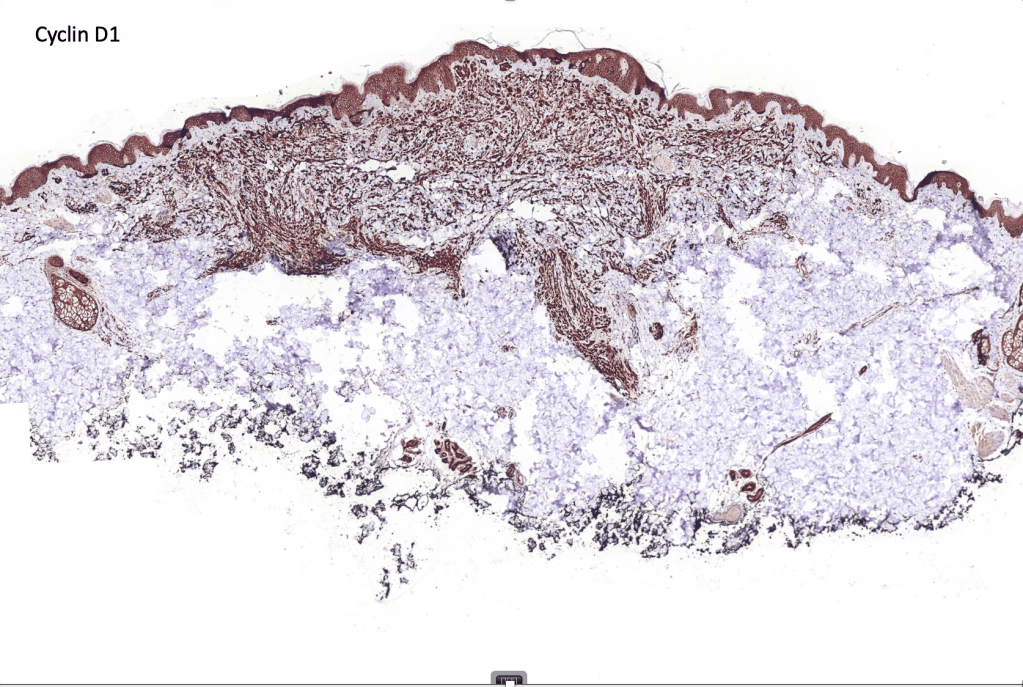

•Strong nuclear & cytoplasmic expression of β catenin, cyclin D1 & LEF1